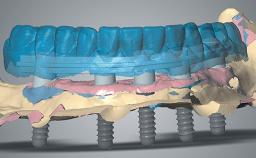

Rehabilitating an Edentulous Maxilla with Three Separate Bridges

A 55-year-old woman was referred to our clinic for implant therapy. She was healthy and had stopped smoking two years previously. Ten years before, the patient had received extensive dental treatment in both jaws. The patient reported that her dental condition had deteriorated progressively since that time. At the time of presentation, the maxillary bridge was loose. The clinical and radiographic examinations revealed a highly compromised situation for all the teeth that supported the bridge and for other teeth.